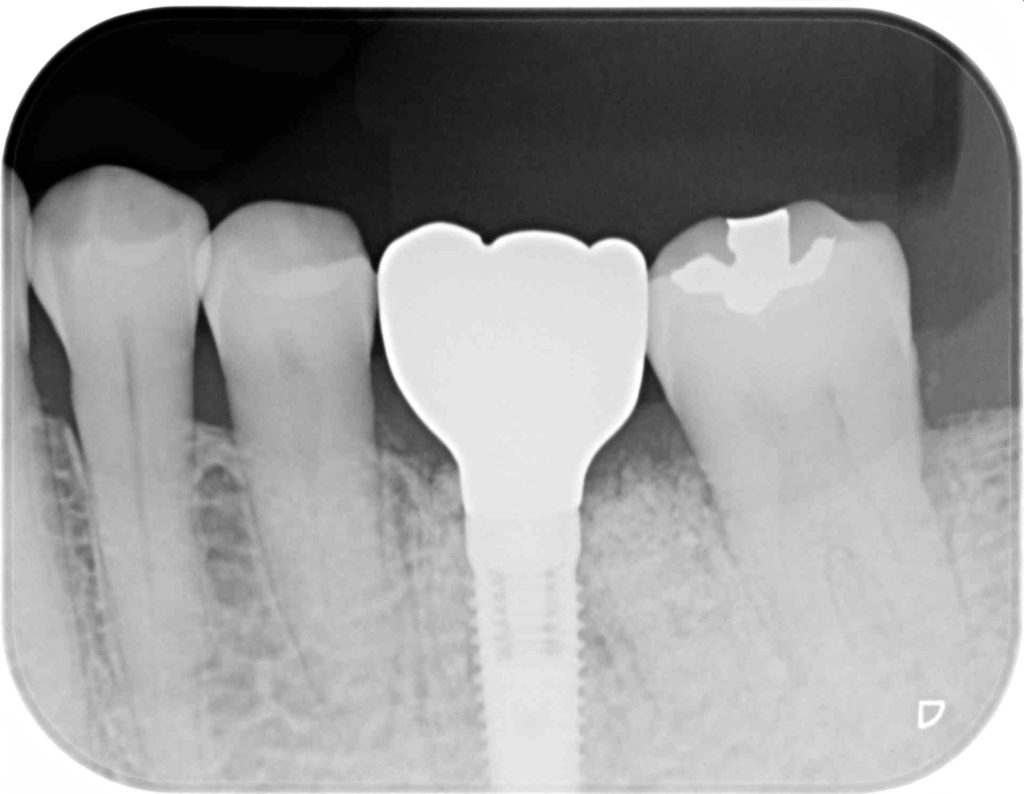

下記の症例は奥歯の抜歯と同時にインプラント治療を行った術後になります。

安全なインプラント治療を提供する為に、SMOPガイドシステムを活用し、術中の痛みやストレスをコントロールする為に麻酔科医による鎮静麻酔を依頼しました。

3ヶ月後、固定式のセラミッククラウンを装着し治療を終了する事が出来ました。

治療費用   約65万円(税抜)